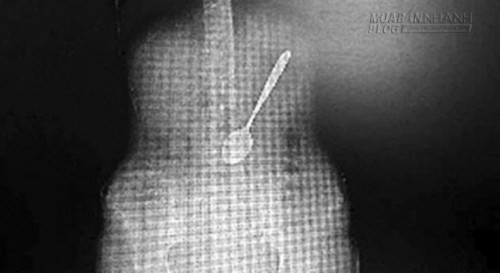

Bác sĩ Ấn Kiện cho biết, qua kiểm tra ông phát hiện trong dạ dày của cô Vương có một chiếc thìa inox dài khoảng 15cm, tình trạng nghiêm trọng hơn nhiều so với những gì các bác sĩ nghĩ ban đầu.

Qua ảnh chụp CT bác sĩ đã phát hiện ra chiếc thìa dài hơn 15cm trong bụng cô Vương và nằm chếch một góc 30 độ. Theo bác sĩ, chiếc thìa có thể trượt vào ruột bất cứ lúc nào. Và nếu điều đó xảy ra, chiếc thìa có thể làm thủng dạ dày gây tổn thương tới nội tạng, thậm chí có thể dẫn tới tử vong. Từ đó, các bác sĩ đã quyết định nhanh chóng lấy chiếc thìa ra ngoài.